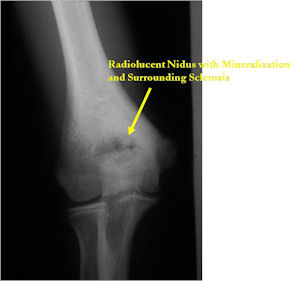

Plain X-Rays:

- Lucent nidus surrounded by a zone of marked sclerosis

- The nidus may demonstrate mineralization/ossification usually from the center outward that appears as a central zone of density within the nidus

- A nidus that is heavily ossified may blend in with the surrounding sclerosis and be difficult to detect on a plain x-ray.